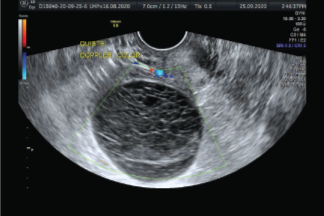

Es un procedimiento no invasivo (no se perfora la piel) que se utiliza para evaluar los órganos y las estructuras dentro de la pelvis femenina. La ecografía pélvica permite una rápida visualización de los órganos y las estructuras pélvicas femeninas, que incluyen el útero, el cuello uterino, la vagina, las trompas de Falopio y los ovarios. La ecografía Doppler también puede mostrar el flujo sanguíneo en determinados órganos pélvicos.

La ecografía pélvica puede proporcionar mucha información sobre el tamaño, la ubicación y la estructura de las masas pélvicas, pero no puede brindar un diagnóstico definitivo del cáncer ni de una determinada enfermedad.